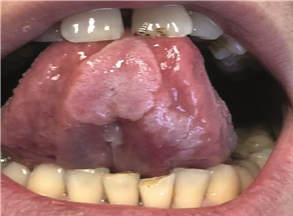

En la zona motivo de consulta, se aprecia en cara ventral de lengua dos placas blanquecinas, una de mayor magnitud en parte media de lengua, y otra de menor extensión en la mitad izquierda de la misma, ambas indoloras (figura 2). Se pregunta al paciente si presenta al momento alguna otra lesión en el cuerpo, lo cual niega. El diagnóstico presuntivo fue de sífilis secundaria, por lo que se solicitó crasis sanguínea y estudios serológicos complementarios de diagnóstico: reacción plasmática rápida (RPR) mide los anticuerpos (AC) liberados por las células huésped dañadas así como también por los treponemas. Dichos AC no sólo se producen como consecuencia de la sífilis sino también en respuesta a enfermedades no treponémicas de naturaleza aguda y crónica donde hay daño tisular. Por dicho motivo se realiza una segunda prueba más específica para detectar AC contra el treponema que causa la sífilis una de ellas es AC anti Treponema pallidum. utilizando el método de la quimioluminiscencia. También hepatitis B, C y VIH a fin de ampliar el protocolo de infecciones de transmisión sexual. El RPR arrojó un valor de 1024 unidades siendo el resultado óptimo: 0–0,001 y la quimioluminiscencia de 28.10 considerando que a partir de 1.0 ya es positiva, mientras que las demás pruebas serológicas resultaron no reactivas (figura 3).

Figura 2. Lesión en cara ventral de lengua.

Confirmado el diagnóstico de sífilis secundaria, se realizó la correspondiente derivación del paciente al centro de salud para recibir el tratamiento adecuado, donde fue medicado con tres dosis de penicilina G benzatínica 2.400.000 UI intramuscular. Post tratamiento se controló al paciente observando una notable mejoría de la lesión, evolucionando a la remisión de la misma (figuras 4A y 4B).

Figura 4A. Control luego de iniciado el tratamiento observándose una reducción de la lesión.

Figura 4B. Control luego de iniciado el tratamiento observándose una reducción de la lesión.